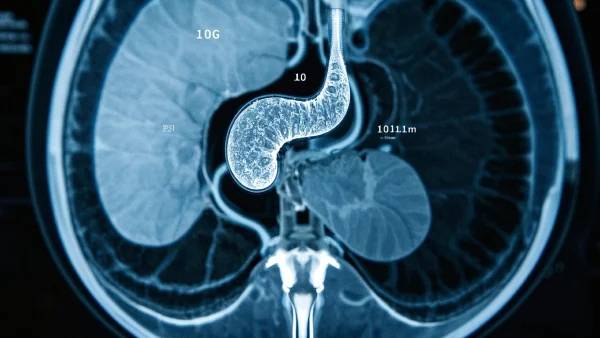

04 胰腺癌在MRI上的典型信号

MRI为胰腺癌“画像”很有讲究。直接看是很难一眼认出的。医生主要看以下几个关键点:

| 影像特征 | 常见描述 | 说明 |

|---|---|---|

| 肿瘤形态 | 多见为局部团块或结节,边界不清 | 肿瘤往往偏小但易侵犯周围组织 |

| 信号强度 | T1低信号,T2稍高甚至等信号 | 这是一种医学“灰阶”表达,癌组织一般信号暗淡 |

| 强化特征 | 动态增强后呈明显低强化 | 与正常腺体相比,癌组织供血较差,强化表现不如正常组织 |

| 主胰管变化 | 可见胰管不规则扩张、截断 | 因为肿瘤堵塞管道,像“小水管堵塞” |

| 周围结构受累 | 可能侵犯邻近血管或胆管,还可见肝脏转移灶 | 晚期时提示肿瘤已发生扩散 |

有时,肿瘤本身不大,但只要看到胰管不规则扩张,并且信号低、强化差,医生往往高度怀疑就是胰腺癌。